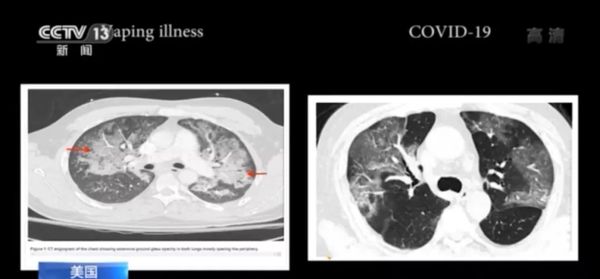

美国电子烟肺炎与新冠肺炎症状几乎无异

2019年7月,美国威斯康星州暴发了神秘电子烟肺炎。随后,这种疾病席卷美国多州。 一位医生称,入院治疗的病人大多呼吸困难、咳嗽、高烧,且大多数有流感的症状。其病症与新冠肺炎症状几乎没有差别,且致病原因未知。

时间上的巧合和肺部CT的相似让人们不禁联想到所谓“电子烟肺炎”和新冠肺炎之间的关系。有网友称,“如果说新冠病毒是实验室泄漏的,我怀疑这就是德特里克堡干的”。